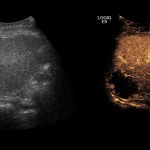

I requisiti per diventare donatori di sangue VIDEO | I requisiti per diventare donatori di sangue, in un video 28 Maggio 2018 Facebook WhatsApp Twitter Pinterest LinkedIn Reddit Donare il sangue è una scelta alla portata di tutti. Ecco i requisiti fondamentali per poter compiere questo gesto di grande generosità Condividi su Facebook (Si apre in una nuova finestra) Facebook Condividi su WhatsApp (Si apre in una nuova finestra) WhatsApp Condividi su Instagram (Si apre in una nuova finestra) Instagram See more Previous article Il dono di Sara Rosignoli ai reparti di Pediatria, Ostetricia e Ginecologia dell’ospedale di Foligno Next article Perugia, diagnosi più rapide e meno invasive grazie alla ecografia con mezzo di contrasto